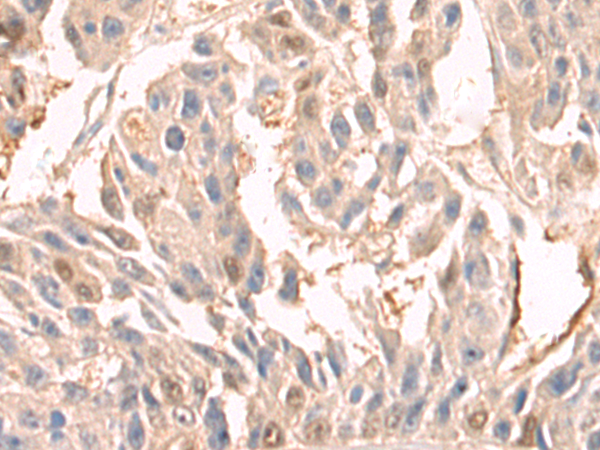

分类: 科研抗体货号: P08304别名: D5D; TU12; FADS6; FADSD5; LLCDL1应用: WB,IHC反应种属: Human, Mouse, Rat